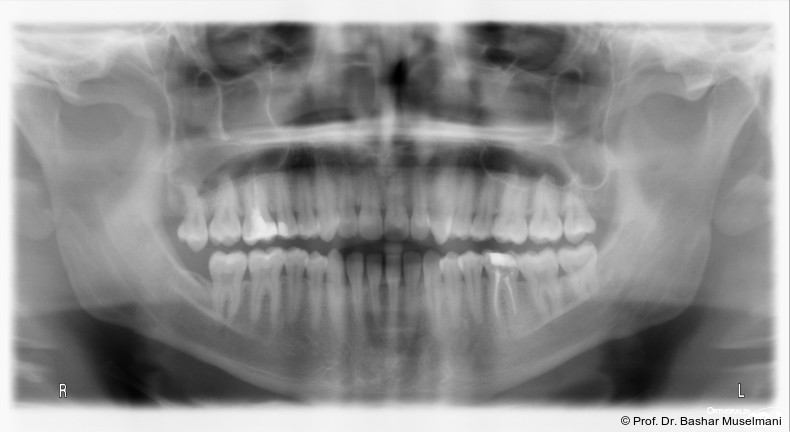

Der Patient (28 Jahre 8 Monate) stellte sich mit einer skelettalen Klasse III sowie einer Mittellinienabweichung nach links vor.

Fernröntgenologische Befunde (Behandlungsbeginn)

• SNA: 81,5°

• SNB: 84,3°

• ANB: −4,9°

• Wits-Wert: −8,4 mm

Klinische Befunde

• leicht konkaves Gesichts- und Mundprofil

• posterior positionierter Unterkiefer (VW)

• retroinkliniert stehende Unterkieferfront

Die Abbildungen 1 bis 3 zeigen die initiale klinische und radiologische Ausgangssituation.